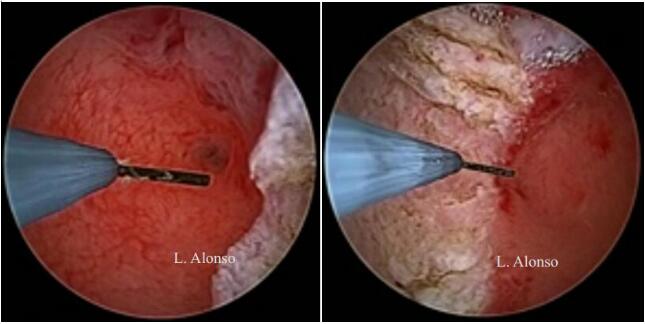

宫腔镜子宫成形术是在子宫纵隔上划开一个横行切口取代了切除。这个切口应在纵隔中间划开,与宫腔前后壁距离相等。参照输卵管开口进行手术有助于保持切口水平,避免损伤正常子宫肌层。选择正确的切口位置是宫腔镜子宫成形术最重要的一部分,但是选择合适切口并不容易。Levent Yasar 和 Ali Süha  发现在亚甲蓝注射后,有2-3mm的蓝色的线,在输卵管开口之间跨过纵隔并且与宫腔前后壁等距离,称此为“Süha-Levent 线” 。这条蓝色的线可以帮助他们选择正确的切口位置。

纵隔手术有两种不同的手术方式,薄化技术和缩短技术。薄化技术是在子宫的每一面将纵隔从底部到顶端做纵行切口,目的是减少纵隔的宽度并改善初始宫腔两侧宫角凹陷中间的基底部残余组织。在缩短技术中,纵隔被横向由顶到底的切开,切口位于纵隔中间,向宫腔前后壁切除残余组织。

上述技术的选择取决于纵隔的宽度和长度,推荐宽阔纵隔使用薄化技术来薄化纵隔,而缩短技术在大多数情况下都适用。